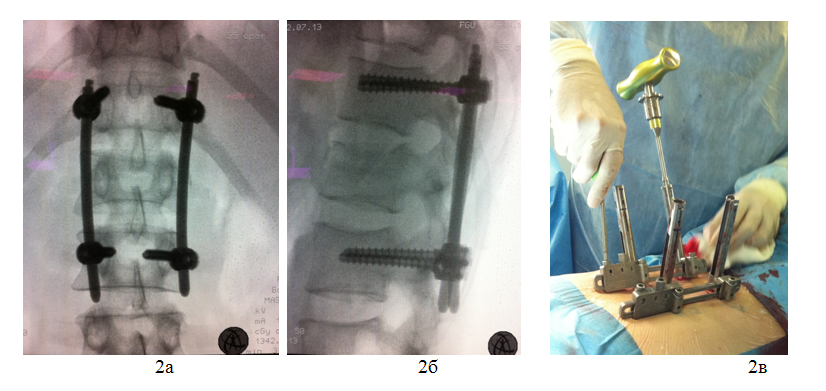

Пострадавший Х., 30 лет, получил травму, упав с высоты 3 метров. При обследовании диагностирован закрытый неосложненный нестабильный компрессионный перелом тела первого поясничного позвонка, посттравматическая кифосколиотическая деформация позвоночника на этом уровне.

После предоперационной подготовки в кратчайшие сроки пациенту выполнена операция: Задняя внутренняя коррекция и фиксация позвоночника чрескожной транспедикулярной системой «Viper 2 3D» DePuy-Synthes.